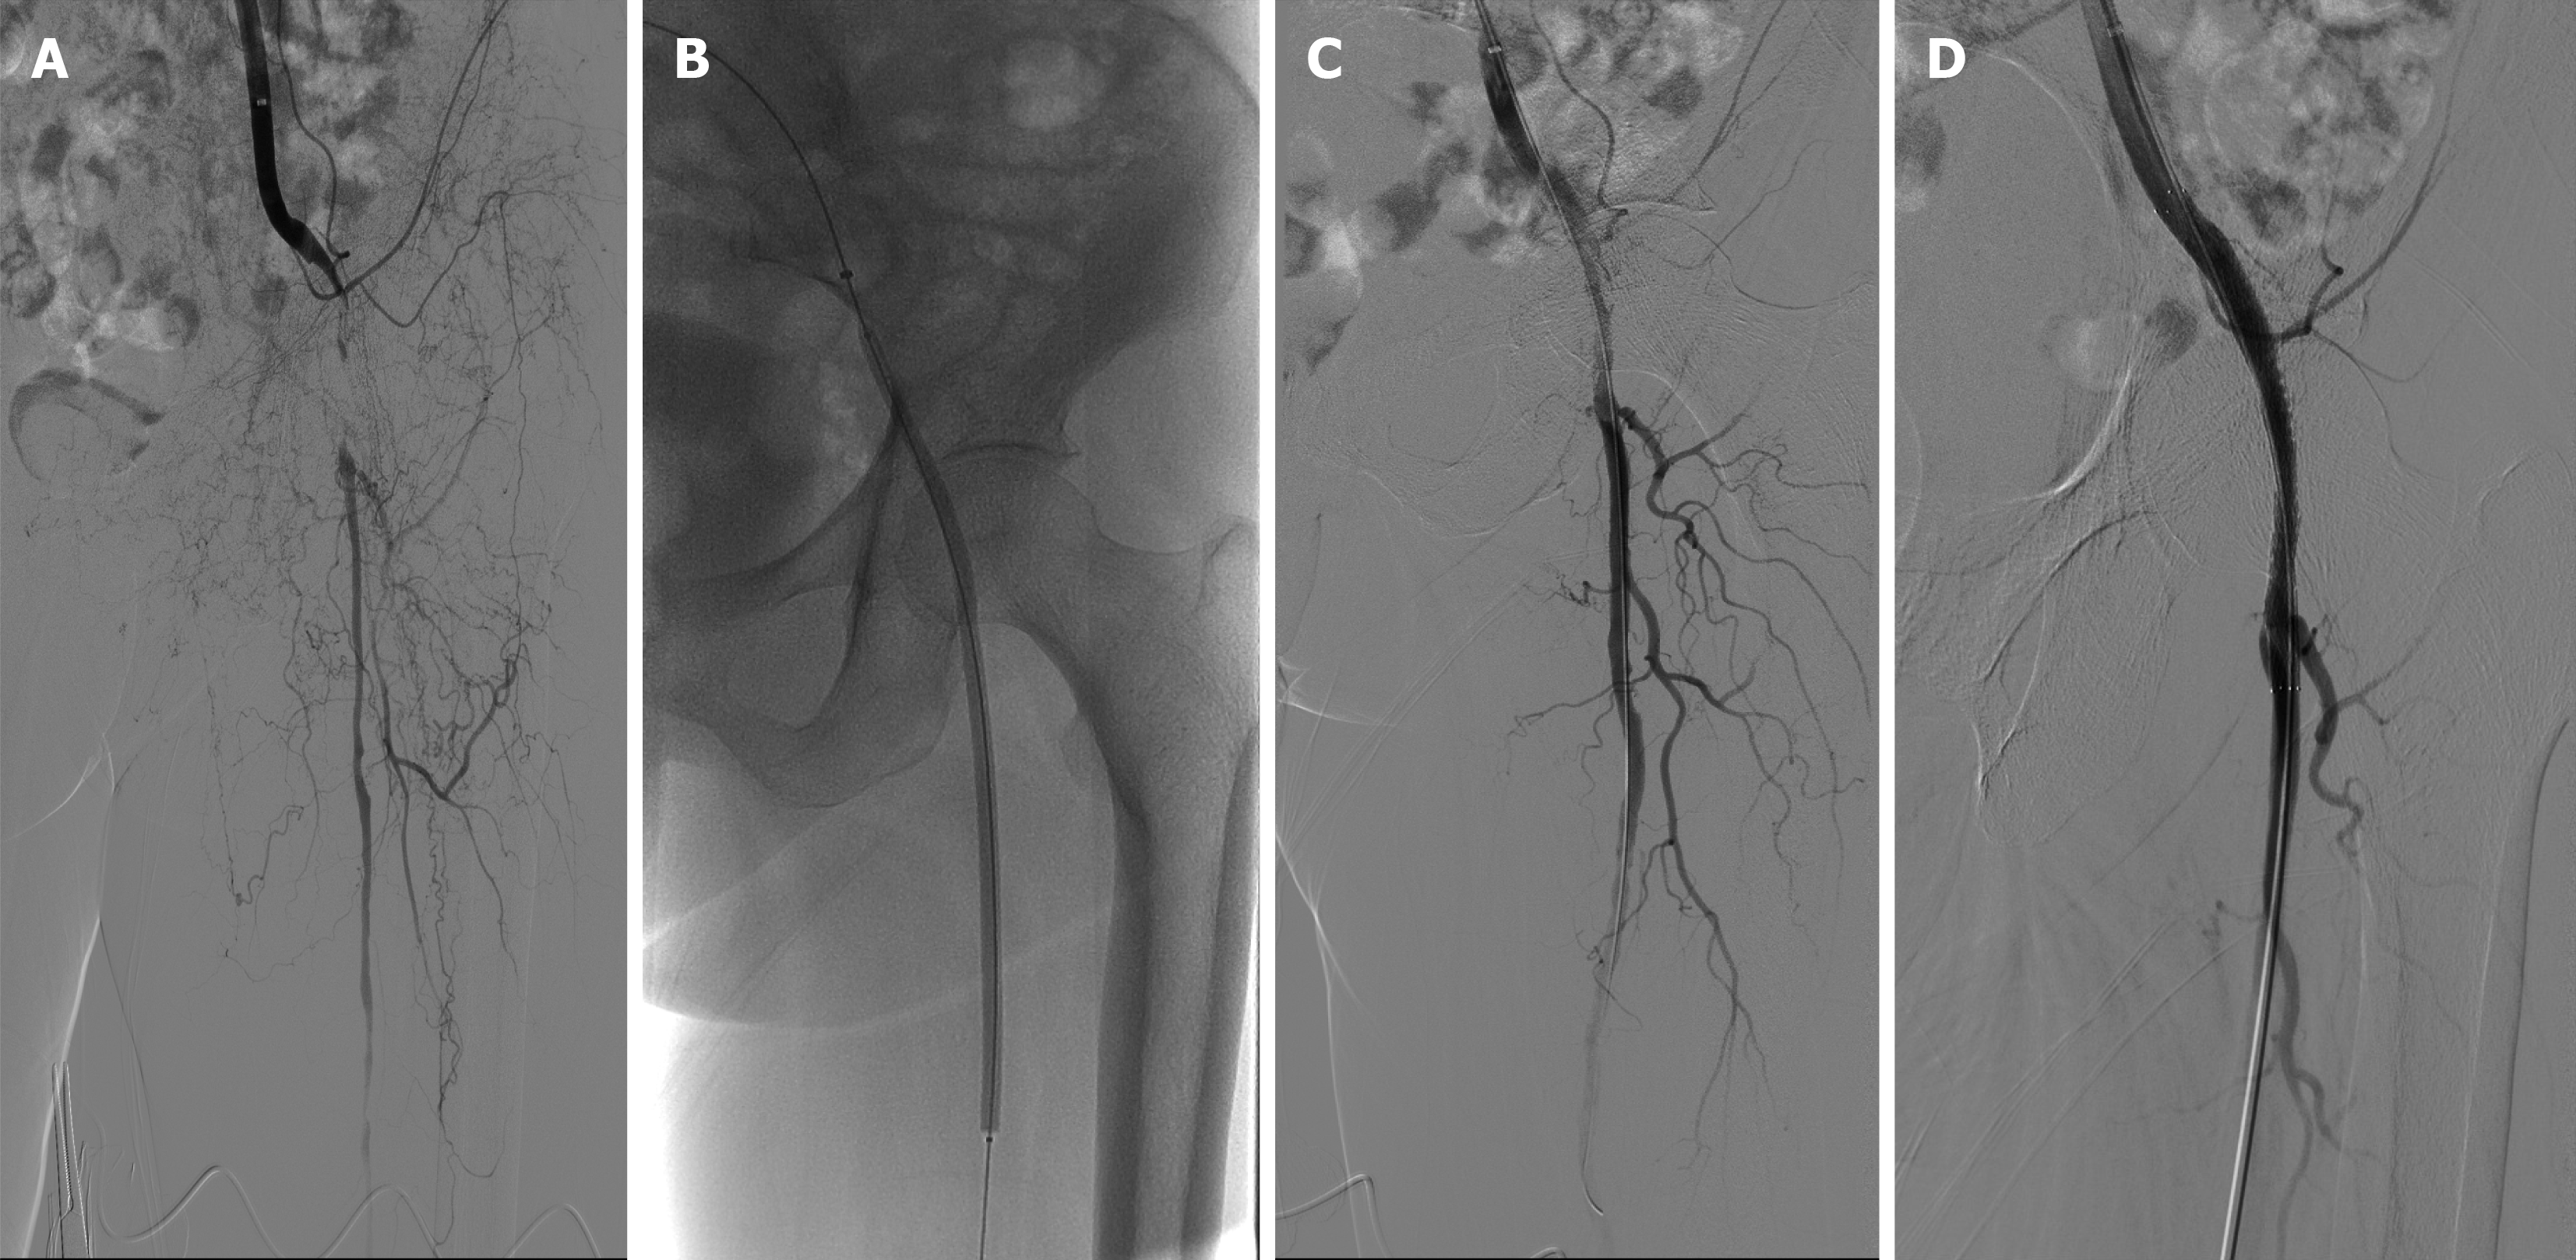

Control group: In addition to the aforementioned basic treatment, patients in this group underwent endovascular revascularization of the affected lower limb. Following routine disinfection and local anesthesia in the groin area, the femoral artery was punctured antegradely or retrogradely to place a vascular sheath. After systemic heparinization, angiography was performed to define the lesion extent (Figure 1A). Subsequently, under roadmap guidance, a guidewire and catheter were used to slowly cross the lesion segment. Based on pre-operative computed tomography angiography images, the vascular preparation method was determined: (1) If the lesion was primarily considered thrombotic, a thrombolysis catheter (Shanghai Meichuang Medical Device Co., Ltd.) was placed, and urokinase (Wuhan Humanwell Pharmaceutical Co., Ltd., National Medicine Permit No. H42021792) was continuously infused at a dose of 400000-600000 IU daily for 2 days. This was followed by staged balloon angioplasty using conventional balloons (Boston Scientific) (Figure 1B); and (2) If the lesion was primarily considered stenosis caused by plaque, direct staged balloon angioplasty was performed using conventional balloons (Boston Scientific). The procedure was concluded if no flow-limiting dissection or residual stenosis < 30% was present post-balloon angioplasty. If flow-limiting dissection (Figure 1C) or residual stenosis ≥ 30% occurred, a bare-metal stent was implanted to improve blood flow (Figure 1D). Post-intervention, patients received antiplatelet therapy with Rivaroxaban (Jilin Province Boda Pharmaceutical Co., Ltd., National Medicine Permit No. H20213352) 2.5 mg twice daily combined with Aspirin (Chenxin Pharmaceutical Co., Ltd., National Medicine Permit No. H20113013) 100 mg once daily for 6 months. All procedures across both study groups were conducted under the same standardized protocol by the same surgical team to ensure consistency and minimize operator bias.